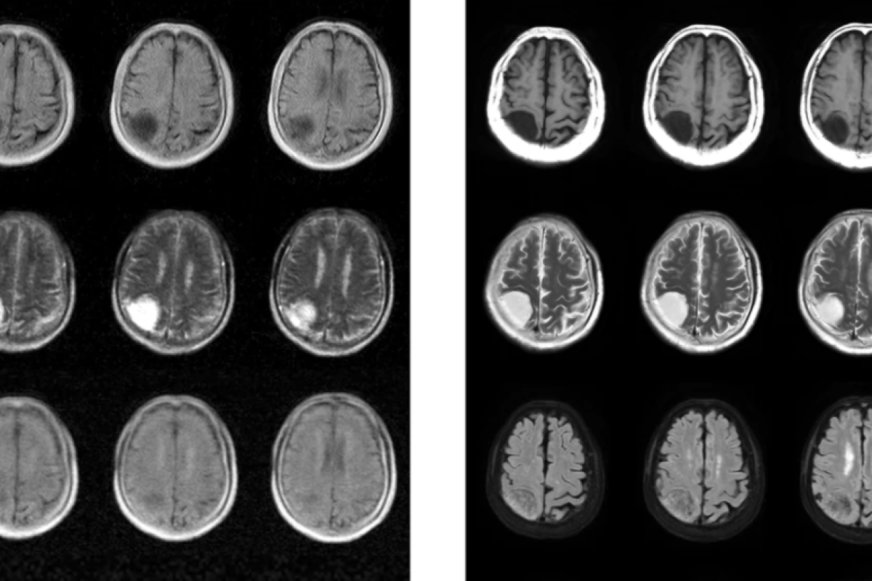

Vedci z Hongkonskej univerzity vyvinuli kompaktnejší a cenovo dostupnejší systém MRI, ktorý využíva oveľa menšie magnetické pole a nevyžaduje tienenie, pričom je schopný diagnostikovať poruchy mozgu u pacientov. Zobrazovanie magnetickou rezonanciou je technika na skenovanie mäkkých tkanív v tele, ktorá je obzvlášť účinná pri diagnostike problémov v mozgu, ako sú nádory, zranenia alebo mŕtvica. Pritom riziká sú tu oveľa nižšie ako pri iných zobrazovacích technikách, ako sú röntgenové lúče alebo CT vyšetrenia.

Menší a lacnejší prenosný prístroj MRI by mohol výrazne rozšíriť využitie technológie. Zatiaľ čo bežná magnetická rezonancia využíva magnetické polia so silou až 3 tesla (T), nový prístroj pracuje s ultranízkym poľom len 0,055 T. Vďaka menšiemu magnetickému poľu zariadenie nepotrebuje magnetickú tieniacu klietku ako tradičné prístroje MRI. Jednoduchosť a menšie rozmery znižujú aj náklady a požiadavky na energiu. Zariadenie môže byť napájané zo štandardnej elektrickej zásuvky a t ...